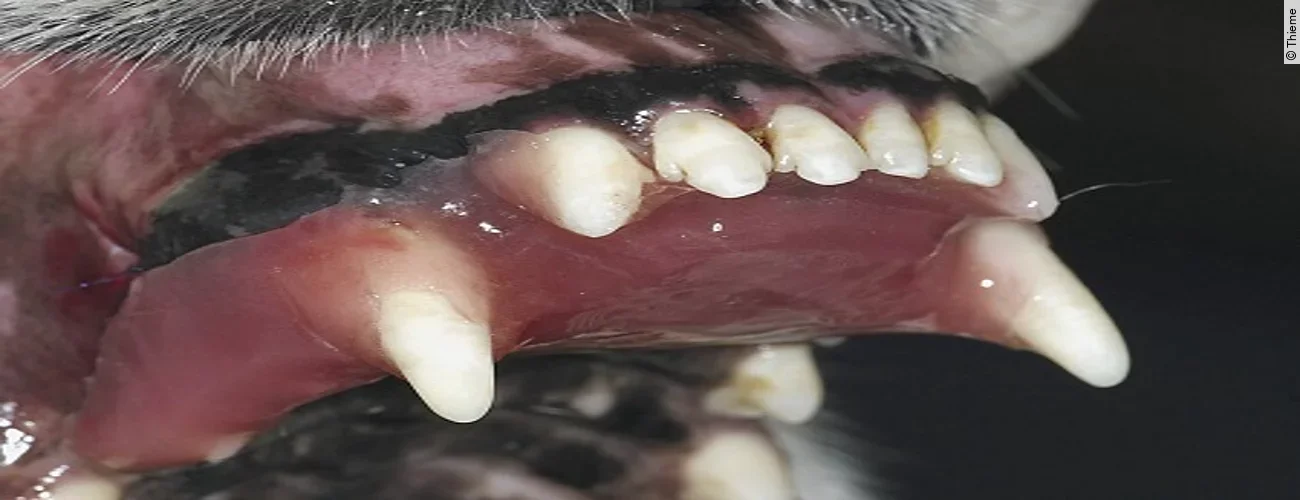

Finales Stadium der Luxation eines Zahnes ist dessen vollständiger Verlust, die Avulsion. Ist der herausgeschlagene Zahn intakt, so kann mittels Replantation eine Wiederherstellung der ursprünglichen Okklusion erreicht werden.

Replantation nach Avulsion Oberkieferfangzahn rechts

Der Originalartikel „Avulsion Oberkieferfangzahn rechts“ stammt aus dem Bild-Atlas der Zahnbehandlungen Hund und Katze; 2. aktualisierte Auflage; 2022.